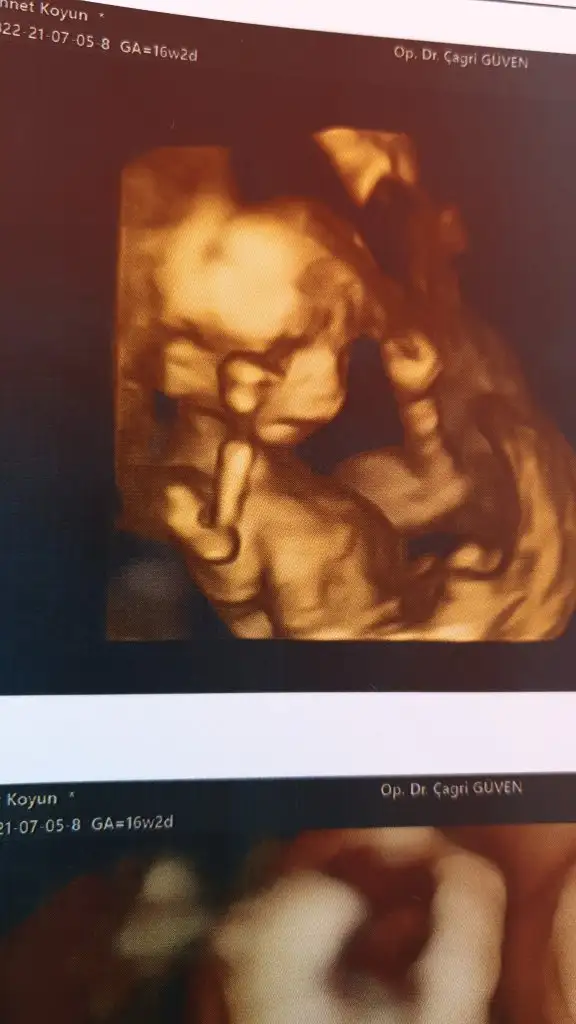

yaa elinin duruşuna maşallah.

En basindan beri surekli elleri ole cnm bugunde surekli ellerini yuzune kapatip aciyodu.. bak 16 haftadaki renkliyi atiyorum orda da ayni...🤣

Bizimkinin 12. Haftadan itibaren tüm ultrason resimlerinde eller kafasında